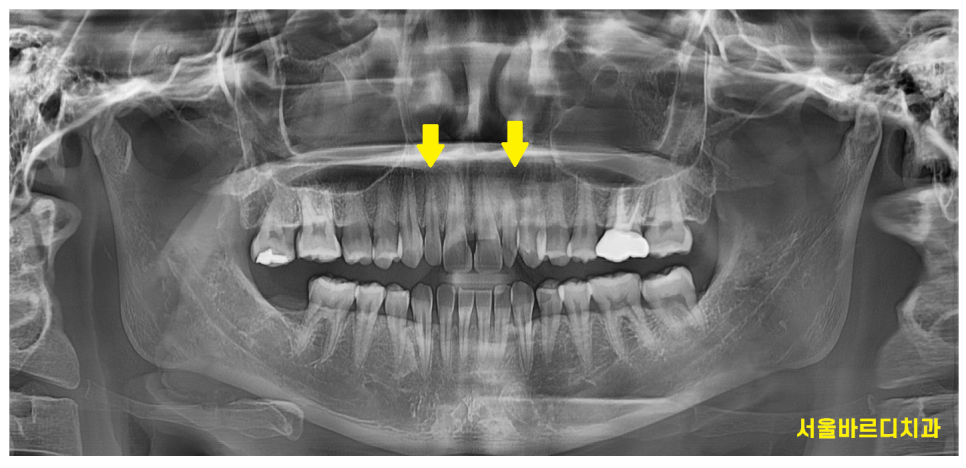

x-ray를 보니 송곳니 ,

맨 앞 대문니에 비해 크기가 작은게 눈에 보이실겁니다.

이러다보니 작은 치아 콤플렉스가 있으셨다고 합니다ㅠㅠ

다른 부위도 아닌 앞니라

사람들에게 잘 보일 수 있는 부분이니까요~